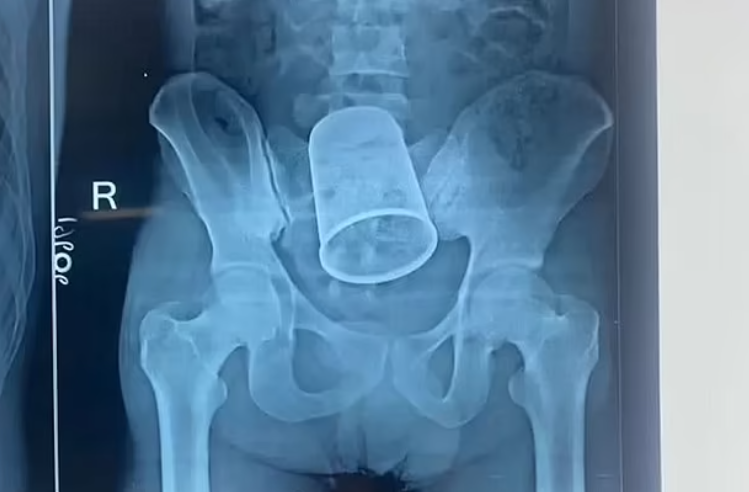

യുവാവിന്റെ വയറ്റില് കുടുങ്ങിയ സ്റ്റീല് ഗ്ലാസ് ശസ്ത്രക്രിയയിലൂടെ പുറത്തെടുത്തു

|റിതേഷ് കുമാറിന്റെ(22) വയറ്റില് നിന്നാണ് ഗ്ലാസ് പുറത്തെടുത്തത്. 5.5 ഇഞ്ച് വലിപ്പമുള്ള ഗ്ലാസാണ് വയറ്റില് കുടുങ്ങിയത്

പാറ്റ്ന: യുവാവിന്റെ വയറ്റില് കുടുങ്ങിയ സ്റ്റീല് ഗ്ലാസ് രണ്ടര മണിക്കൂര് നീണ്ട ശസ്ത്രക്രിയയിലൂടെ പുറത്തെടുത്തു. പാറ്റ്ന, ബേട്ടിയ സ്വദേശിയായ റിതേഷ് കുമാറിന്റെ(22) വയറ്റില് നിന്നാണ് ഗ്ലാസ് പുറത്തെടുത്തത്. 5.5 ഇഞ്ച് വലിപ്പമുള്ള ഗ്ലാസാണ് വയറ്റില് കുടുങ്ങിയത്.

ശക്തമായ വേദനയെയും രക്തസ്രാവത്തെയും തുടര്ന്ന് ഒക്ടോബര് 4നാണ് റിതേഷിനെ പാറ്റ്ന മെഡിക്കല് കോളേജ് ആശുപത്രിയില് പ്രവേശിപ്പിച്ചത്. മദ്യപിച്ചെത്തിയ യുവാവിന്റെ ഗുഹ്യഭാഗത്ത് ചോരയൊലിക്കുന്നുണ്ടായിരുന്നു. ഗ്ലാസ് ഗുഹ്യഭാഗത്തു കൂടിയാണ് വയറിനുള്ളിൽ എത്തിയതെന്ന് ഡോക്ടർമാർ പറഞ്ഞു. ശസ്ത്രക്രിയ അപകടകരമായിരുന്നുവെന്നും എന്നാല് 11 ഡോക്ടര്മാരടങ്ങുന്ന സംഘം സുരക്ഷിതമായി ഗ്ലാസ് പുറത്തെടുത്തുവെന്നും ശസ്ത്രക്രിയക്ക് നേതൃത്വം നല്കിയ ഡോ. ഇന്ദ്ര ശേഖര് കുമാര് പറഞ്ഞു.